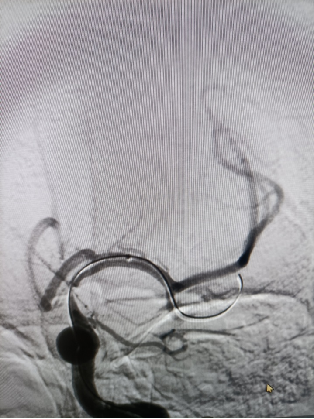

治疗中路径显示患者右侧颈内动脉的迂曲。

导丝怎么扩【载药时代 球扩天下】NOVA DES®颅内药物洗脱支架在颈内动脉颅内段重度狭窄的应用两例!滕州市中心医院&山西医科大学第二医院_https://www.jmylbn.com_新闻资讯_第16张

导引导管到位,导丝通过病变。

导丝怎么扩【载药时代 球扩天下】NOVA DES®颅内药物洗脱支架在颈内动脉颅内段重度狭窄的应用两例!滕州市中心医院&山西医科大学第二医院_https://www.jmylbn.com_新闻资讯_第17张

球囊通过病变扩张血管后,残余狭窄30%,局部血管夹层可疑。远端通路导管在球囊导管的引导下通过迂曲的C3、C4段,抵达病变血管近端。